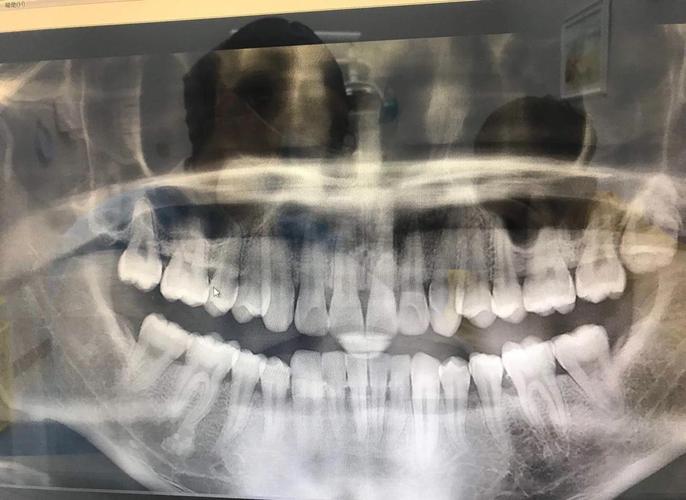

| 全景片(曲面断层片) | 观察全口牙齿的发育、萌出情况,牙根形态、长度,牙槽骨高度,以及是否存在埋伏牙、多生牙、囊肿等 | 常规初诊筛查,了解牙齿整体排列和牙根状态 |